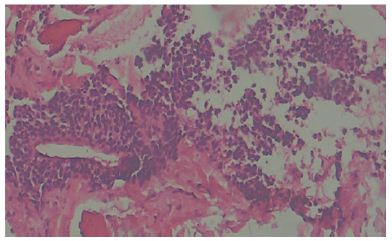

On the distal part of the incision further dissection was done and recurrent branch of radial artery was ligated (Figure 5) to avoid injury to it. Bicepital tuberosity on radius was identified and bed prepared (Figure 6). An anchor screw was passed into it and with the fibre wire, tendon was re attached (Figure 7), as we expected there was enormous tension on tendon and hence a long arm slab in 1100 of flexion and supination was given. Patient was discharged on second post op day and at one month follow up slab and sutures were removed, elbow mobilisation started (Figure 8). Wound was healed well and at 2 months post of he had near normal range of movement and without any pain and quick DASH score improved to 11 at 2 months post op and it is improving further.